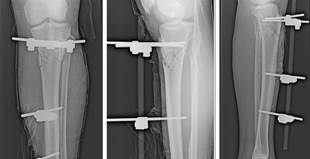

Bajo anestesia subaracnoidea, se realiza la asepsia y antisepsia en miembro inferior izquierdo, se coloca campos operatorios y se inicia desbridamiento de bordes de zona cruenta la cual se amplía con una incisión longitudinal proximal y distal de 3 cm aproximadamente. Se continua con un lavado profuso con antisépticos y solución salina. Se procede a realizar curetaje de extremos óseos y fijación con tutores externos: 2 pines transversales en fragmento proximal y 2 pines en fragmento distal (TUTOR EXTERNO AO).

Figura 1. Colocación de tutores externos

Al día 43, se retiran los tutores externos y se coloca osteosíntesis placa de tibia izquierda y junto con Cirugía Plástica se le realiza una cobertura con colgajo de gastrocnemio medial.

Se procede bajo anestesia raquídea, a realizar la asepsia y antisepsia, se coloca campos quirúrgicos y se procede al retiro del sistema de tutores externos. Luego se realiza un lavado profuso con desbridamiento de tejido desvitalizado. Se prolonga una incisión de aproximadamente 3 cm hacia proximal. Se hace una fijación medial con placa en T de 6 orificios y una fijación lateral con placa de DCP 4.5 de 4 orificios. Se verifica el correcto posicionamiento con el intensificador de imágenes.

Figura 5. Osteosíntesis de tibia izquierda